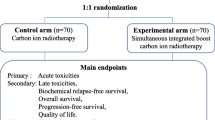

The clinical outcomes of 253 patients with prostate cancer who were treated with CIRT delivered using the spot scanning method between December 2015 and December 2017 were retrospectively analyzed. The irradiation dose was set at 51.6 Gy (relative biological effectiveness) delivered in 12 fractions over 3 weeks. Biochemical relapse was defined using the Phoenix definition. Toxicities were assessed according to CTCAE version 4.0. Results: The median patient age was 70 (47–86) years. The median follow-up duration was 35.3 (4.1–52.9) months. According to the D’Amico classification system, 8, 88, and 157 patients were classified as having low, intermediate, and high risks, respectively. Androgen deprivation therapy was administered in 244 patients. The biochemical relapse-free rate in the low-, intermediate-, and high-risk groups at 3 years was 87.5, 88.0, and 97.5%, respectively (P = 0.036). Grade 2 acute urinary toxicity was observed in 12 (4.7%) patients. Grade 2 acute rectal toxicity was not observed. Grade 2 late urinary toxicity and grade 2 late rectal toxicity were observed in 17 (6.7%) and 3 patients (1.2%), respectively. Previous transurethral resection of the prostate was significantly associated with late grade 2 toxicity in univariate analysis. The predictive factor for late rectal toxicity was not detected.

The BFS rate is presented in Fig. 1. The BFS rates in the low-, intermediate-, and high-risk groups at 3 years were 87.5, 88.0, and 97.5%, respectively (p = 0.036). Biochemical relapse was observed in 14 patients. Biochemical relapse was observed at a median of 25.7 (range, 0.8–42.2) months after CIRT. Significant difference was observed between age and biochemical relapse. The median ages with and without biochemical relapse were 64 (range, 50–86) and 70 (range, 47–85) years, respectively (p = 0.007). Significant differences were not observed in other patient characteristics. In eleven of fourteen patients, the PSA level was decreased without any treatment such as ADT. Two patients received ADT immediately after the diagnosis of PSA failure without radiological confirmation of clinical recurrence. Clinical recurrence was observed in one patient. A patient who was classified as high-risk group experienced pelvic node and lung metastases at 36.6 months after CIRT.

The late GI toxicity grades were one in 12 patients (4.7%) and two in three patients (1.2%). Grade 3 or greater late GI toxicity was not observed. All late GI toxicities were rectal hemorrhage. Grades 1 and 2 GI toxicities were observed in median durations of 14.4 (range, 10.0–23.6) and 9.1 (range, 4.8–13.4) months after CIRT, respectively (p = 0.167). The cumulative incidence rate of any-grade late rectal toxicity is shown in Fig. 2. The 3-year cumulative incidence rate of any-grade late rectal toxicity was 6.1%.